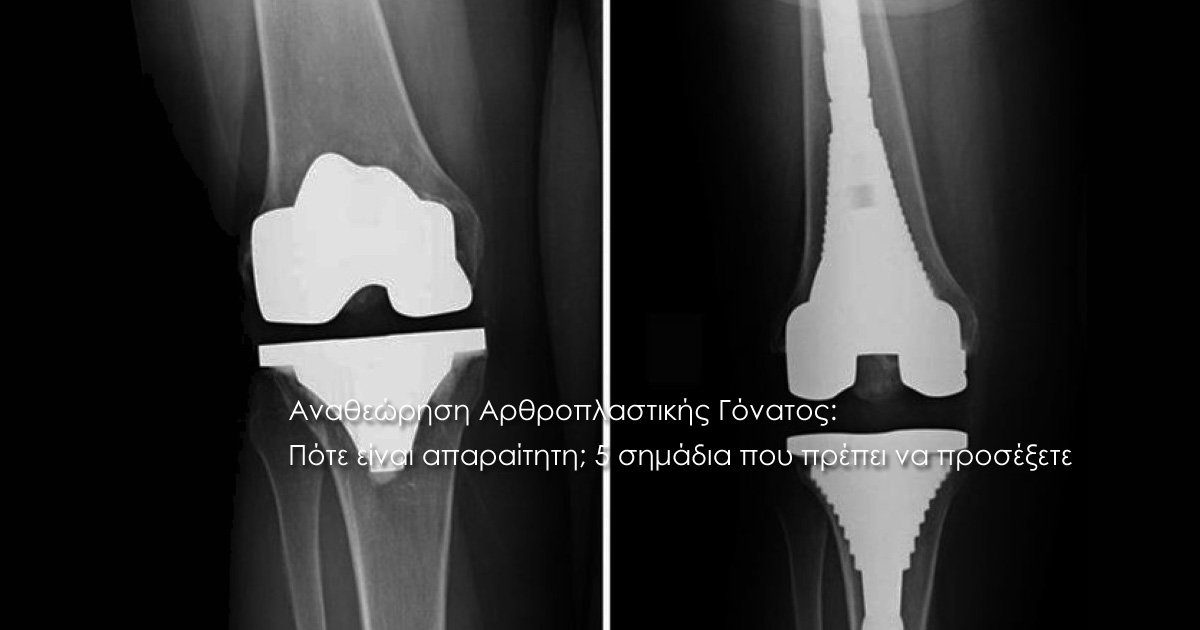

Η αναθεώρηση (revision) της αρθροπλαστικής γόνατος είναι μια εξειδικευμένη επέμβαση όπου ο ορθοπαιδικός χειρουργός αντικαθιστά τα φθαρμένα ή χαλαρωμένα τμήματα της παλιάς πρόθεσης με νέα. Αν και η ολική αρθροπλαστική γόνατος είναι μία από τις πιο επιτυχημένες επεμβάσεις της σύγχρονης ιατρικής, υπάρχουν περιπτώσεις όπου η αρχική πρόθεση παύει να λειτουργεί σωστά. Πότε μπορεί να συμβεί αυτό; Η ανάγκη για επανεπέμβαση δεν έχει σταθερό χρόνο εμφάνισης, αλλά συνήθως ακολουθεί δύο μοτίβα:

Η αναβολή μιας αναθεώρησης μπορεί να οδηγήσει σε μεγαλύτερη απώλεια οστού, κάνοντας τη δεύτερη επέμβαση πολύ πιο δύσκολη. Ο εξειδικευμένος ορθοπαιδικός θα χρησιμοποιήσει ακτινογραφίες, σπινθηρογράφημα ή ειδικές εξετάσεις αίματος για να επιβεβαιώσει την αιτία του προβλήματος. Αν αναγνωρίζετε κάποιο από τα παραπάνω συμπτώματα, δεν σημαίνει απαραίτητα ότι θα καταλήξετε στο χειρουργείο, αλλά ότι απαιτείται άμεση αξιολόγηση.